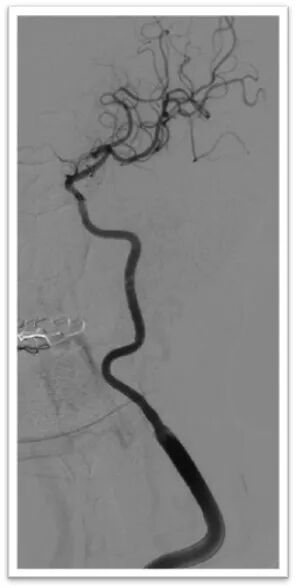

图4:DSA提示主动脉弓为牛角弓,左侧颈总动脉发自头臂干动脉,右侧颈内动脉造影提示前交通动脉开放,呈双干大脑前动脉,左侧大脑前动脉通过软膜支向左侧大脑中动脉供血区域代偿,双侧椎动脉均势供血,左侧大脑后动脉通过软膜支向前代偿供血;左侧颈总动脉闭塞,残端呈杯口状,近端可见白色血栓影,初步考虑栓塞性闭塞。